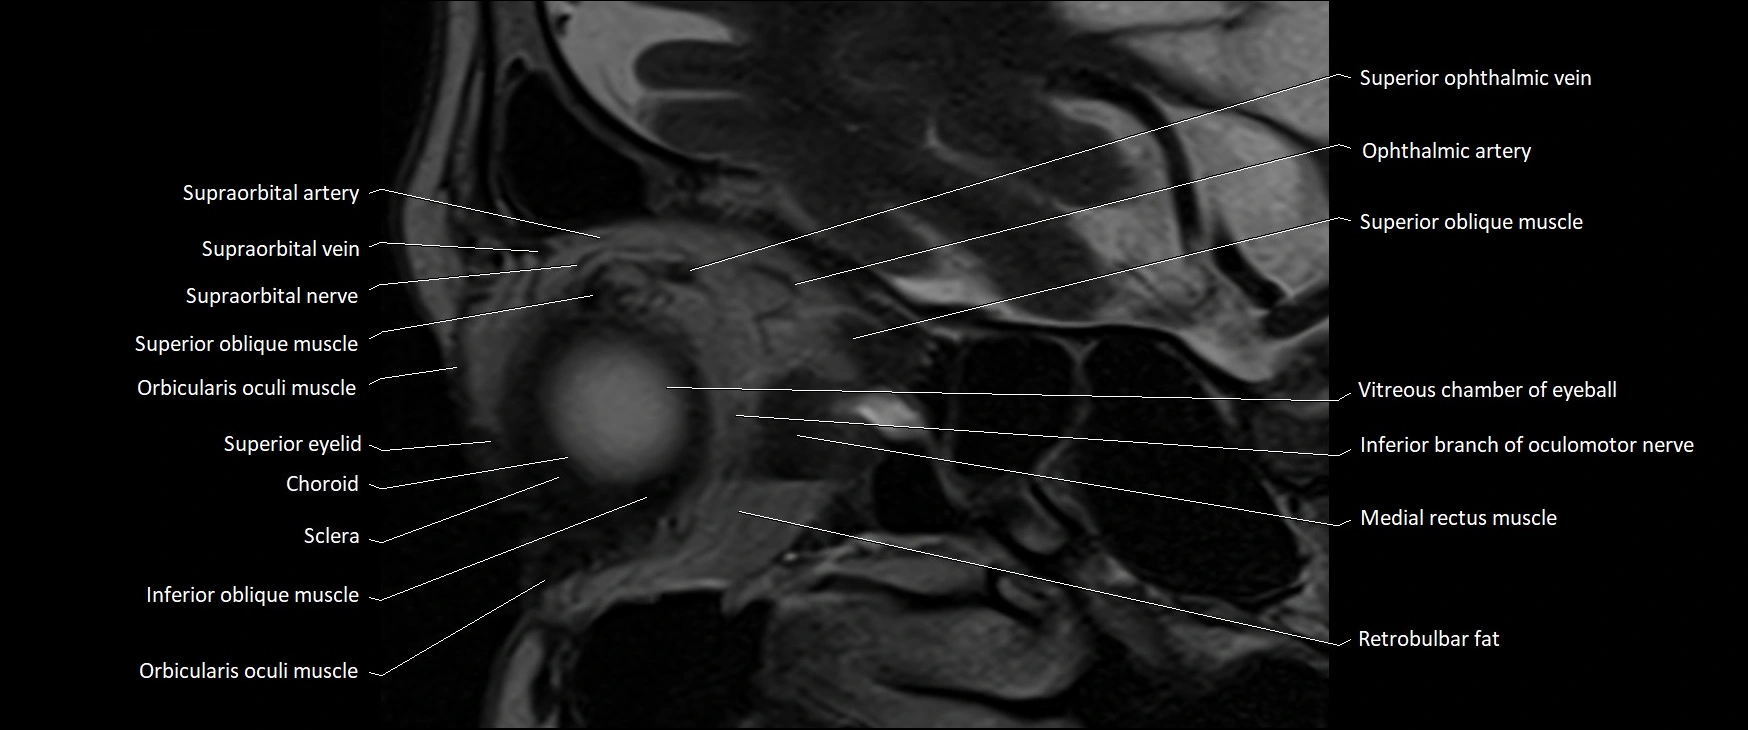

- Orbicularis oculi muscle

- Superior oblique muscle

- Superior ophthalmic vein

- Medial rectus muscle

- Retrobulbar fat

- Sclera

- Choroid

- Inferior oblique muscle

- Superior eyelid

- Supraorbital artery

- Supraorbital nerve

- Supraorbital vein

- Vitreous chamber of eyeball